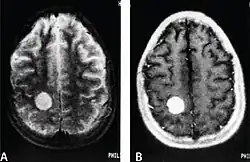

MRI of a cardiac angiosarcoma that has metastasised to the brain. | |

Primary cardiac angiosarcoma is an angiosarcoma that arises in the heart. Despite being very rare they are the most common malignant primary heart tumor with 10–25%[12][3] of cases being angiosarcomas. Symptoms may include shortness of breath, chest pain (46%[12]), hypotension and syncope. Superior vena cava syndrome is reportedly a complication of cardiac angiosarcoma.[7] Due to the non-specificity of symptoms and rarity of the disease it is often missed by doctors and initial diagnosis may be delayed. A 2012 study reported that 56% of patients presented with pericardial effusion with or without cardiac tamponade.[12] The most common finding on imaging is cardiomegaly. Prognosis is generally very poor with a mean survival rate of three months to four years following diagnosis.[7] Metastasis at time of diagnosis is common.[12]